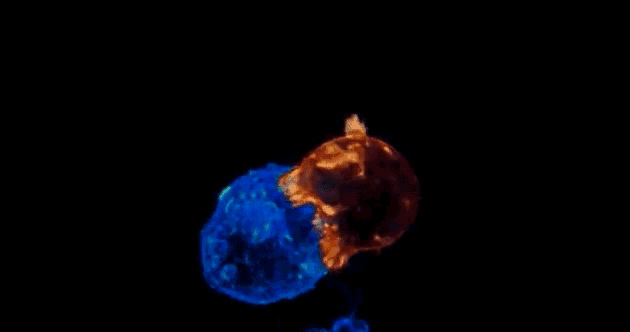

细胞(红色)攻击癌细胞(蓝色)